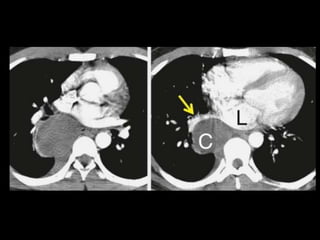

Embolia Pulmonar

Diagnóstico de embolia aguda na TC com contraste

é baseado na visualização direta de falhas de

enchimento parciais ou completas dentro das

artérias pulmonares;

Sinal da “rosca”;

Sinal do “trilho de trem”;

Outro sinal útil: formação de ângulos agudos com a

parede vascular, a perda completa da opacificação e

o aumento do diâmetro do vaso acometido.

Embolia Pulmonar Diagnóstico deembolia aguda na TC com contraste é baseado na visualização direta de falhas de enchimento parciais ou completas dentro das artérias pulmonares; Sinal da “rosca”; Sinal do “trilho de trem”; Outro sinal útil: formação de ângulos agudos com a parede vascular, a perda completa da opacificação e o aumento do diâmetro do vaso acometido.